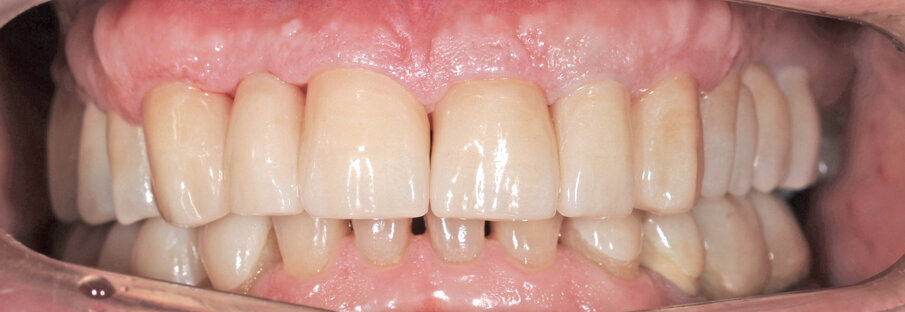

Il paziente utilizza questi secondi provvisori per otto settimane, durante le quali conferma la buona integrazione dei restauri e la soddisfacente funzione occlusale. Ciò è verificato con l’esecuzione di una nuova axiografia elettronica che già a due settimane dalla consegna evidenzia una buona risposta muscolare al nuovo design occlusale ed alla nuova postura mandibolare in TRP (Figg. 43-46). Provvediamo infine alle impronte per la costruzione dei manufatti definitivi in Zirconia-ceramica. I modelli sono scansiti in laboratorio con inEos X5 (Dentsply Sirona) su exocad (Figg. 47-49), ed una seconda scansione viene eseguita con i provvisori del Paziente posizionati sui modelli (Figg. 50-52). Il CAD consente di eseguire un matching fra le due scansioni, per cui i secondi provvisori utilizzati in TRP, con funzione occlusale sequenziale già completamente programmata, sono utilizzati per definire le morfologie dentali definitive di tutti gli elementi da restaurare (Figg. 53, 54) secondo il rapporto intermascellare definito (Figg. 55-58). Si esegue quindi fresatura al CAM della protesi definitiva in zirconia (Figg. 59, 60), la stratificazione e finitura ed infine la consegna al Paziente con cementazione in Panavia V5 (Figg. 61-65).